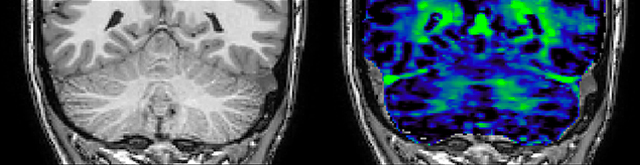

T1 - Weighted, Myelin Water Fraction Superimposed

Spinal cord coverage

Smaller, more isotropic voxels

Excellent detail in quantitative maps

Images courtesy of Adam Dvorak, Department of Physics and Astronomy, University of British Columbia

QSM based on a Compressed SENSE multi-echo SWI.